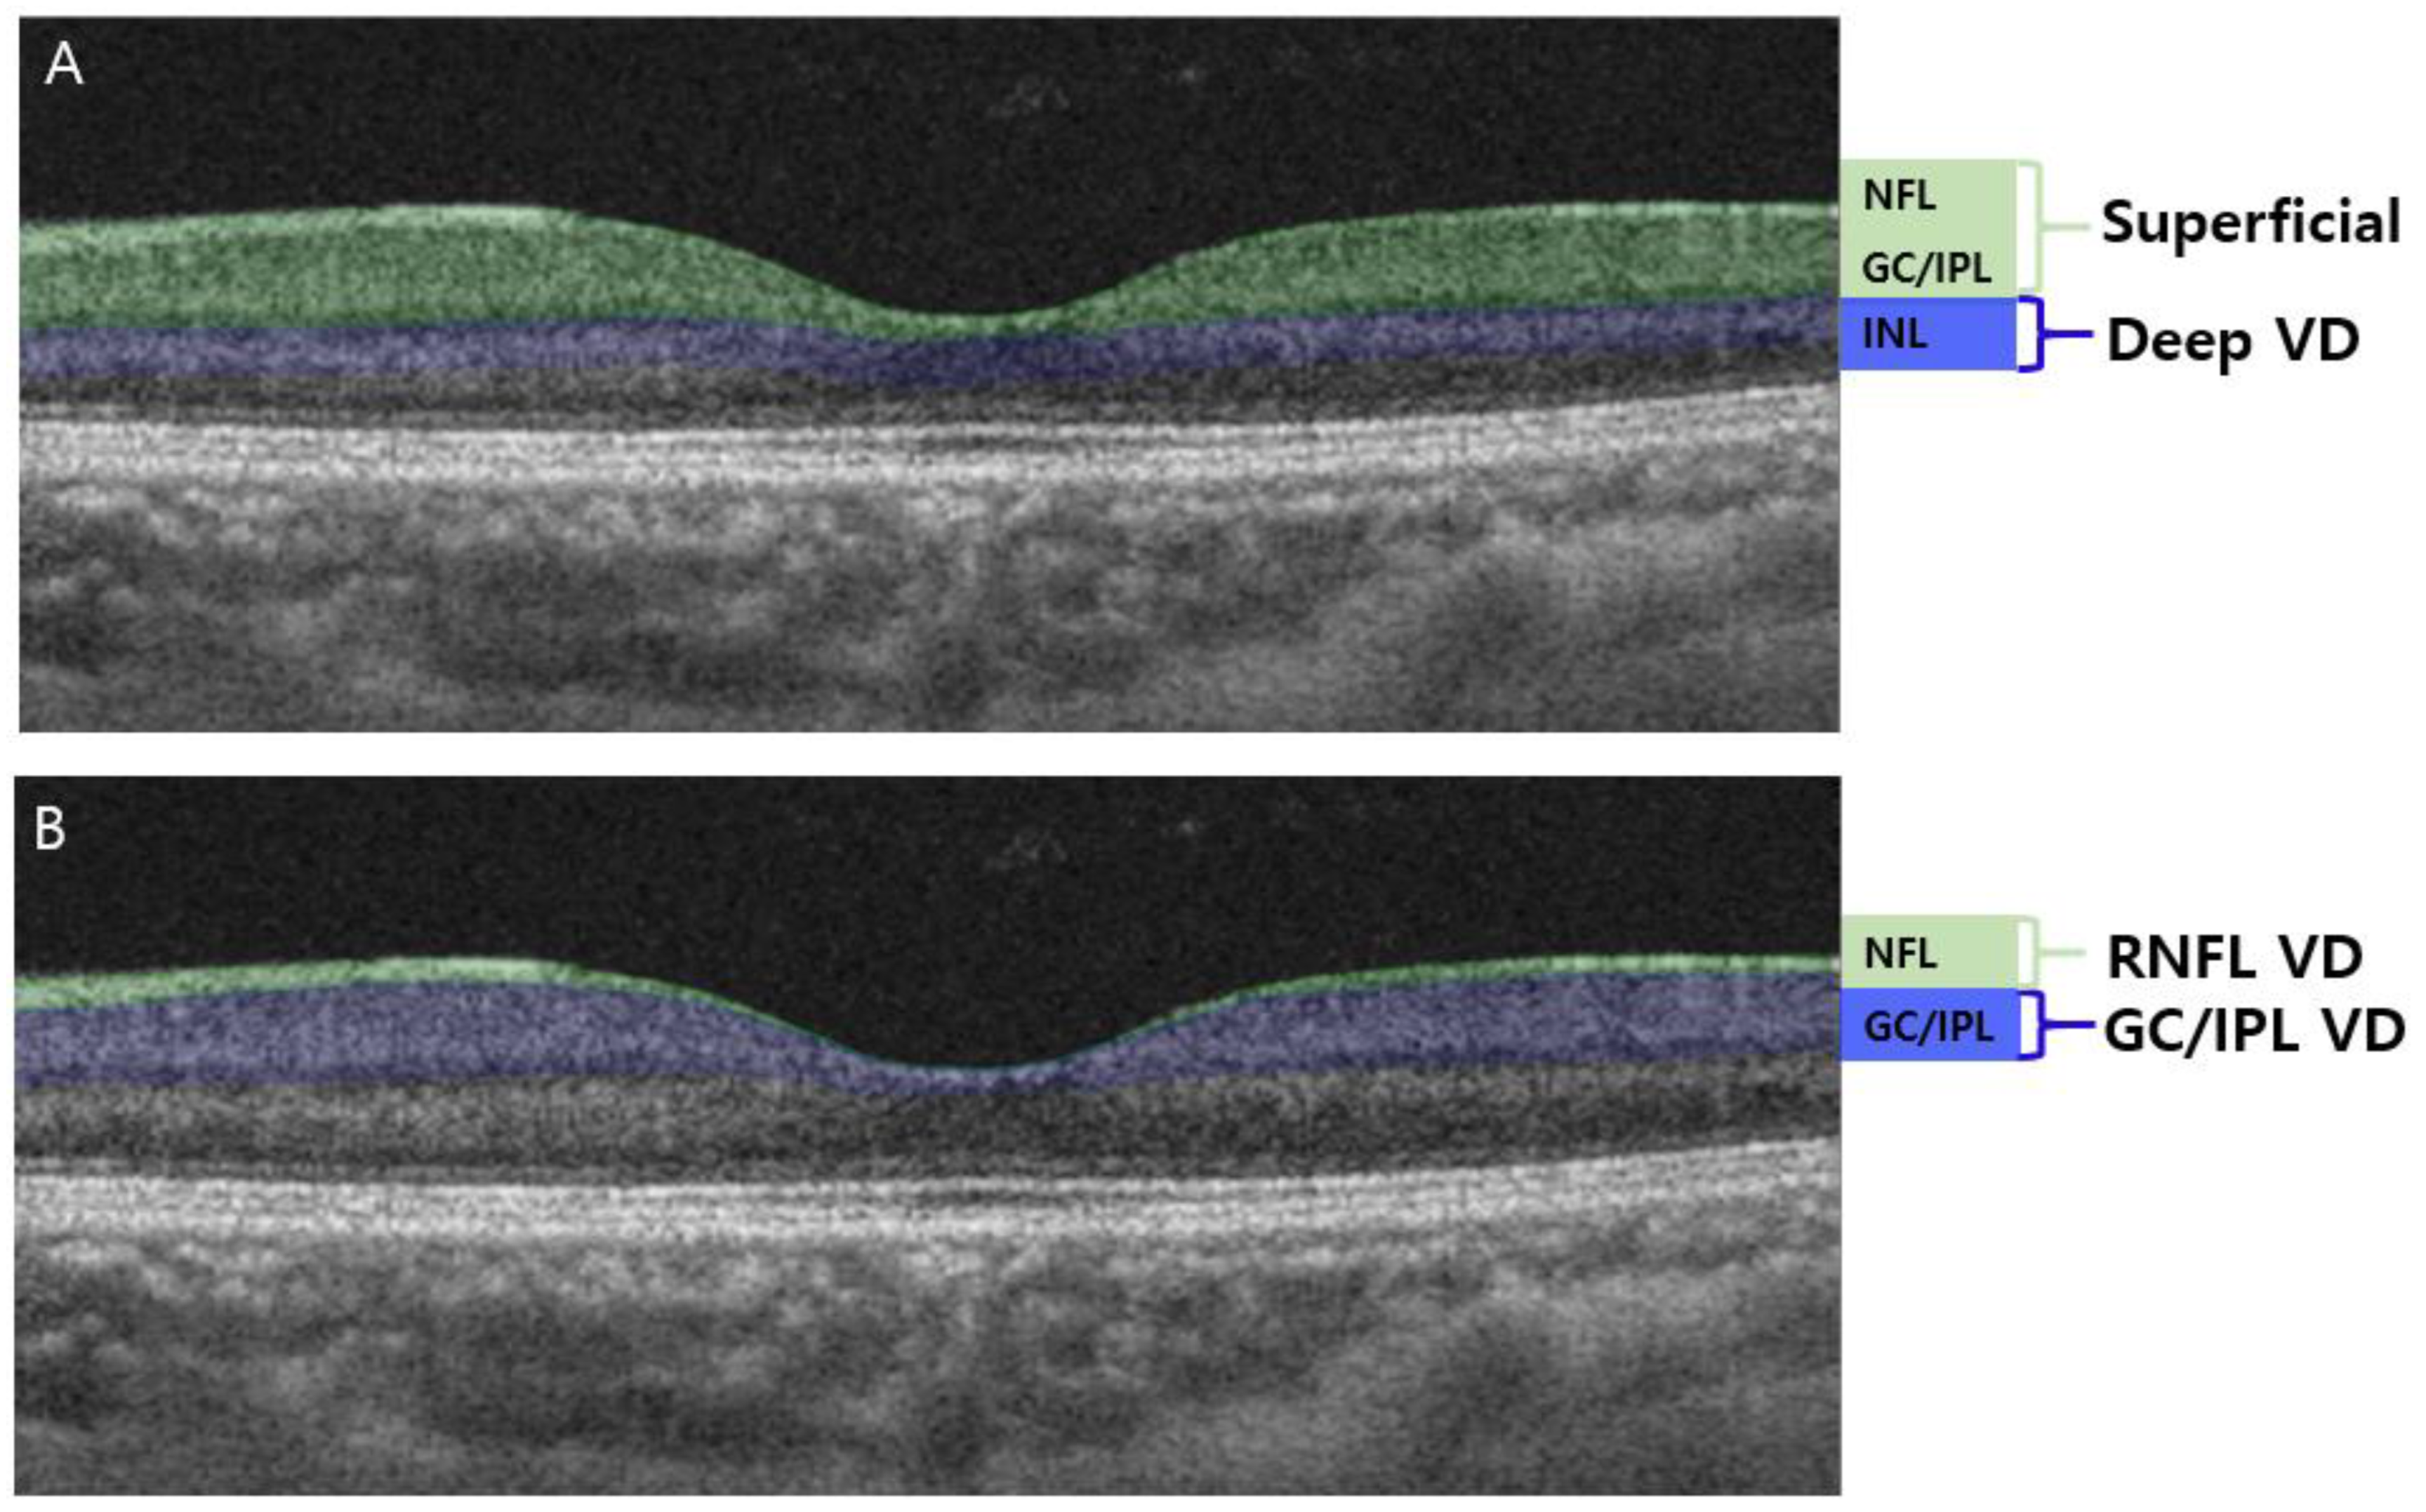

2.2. OCTA and VD Measurement